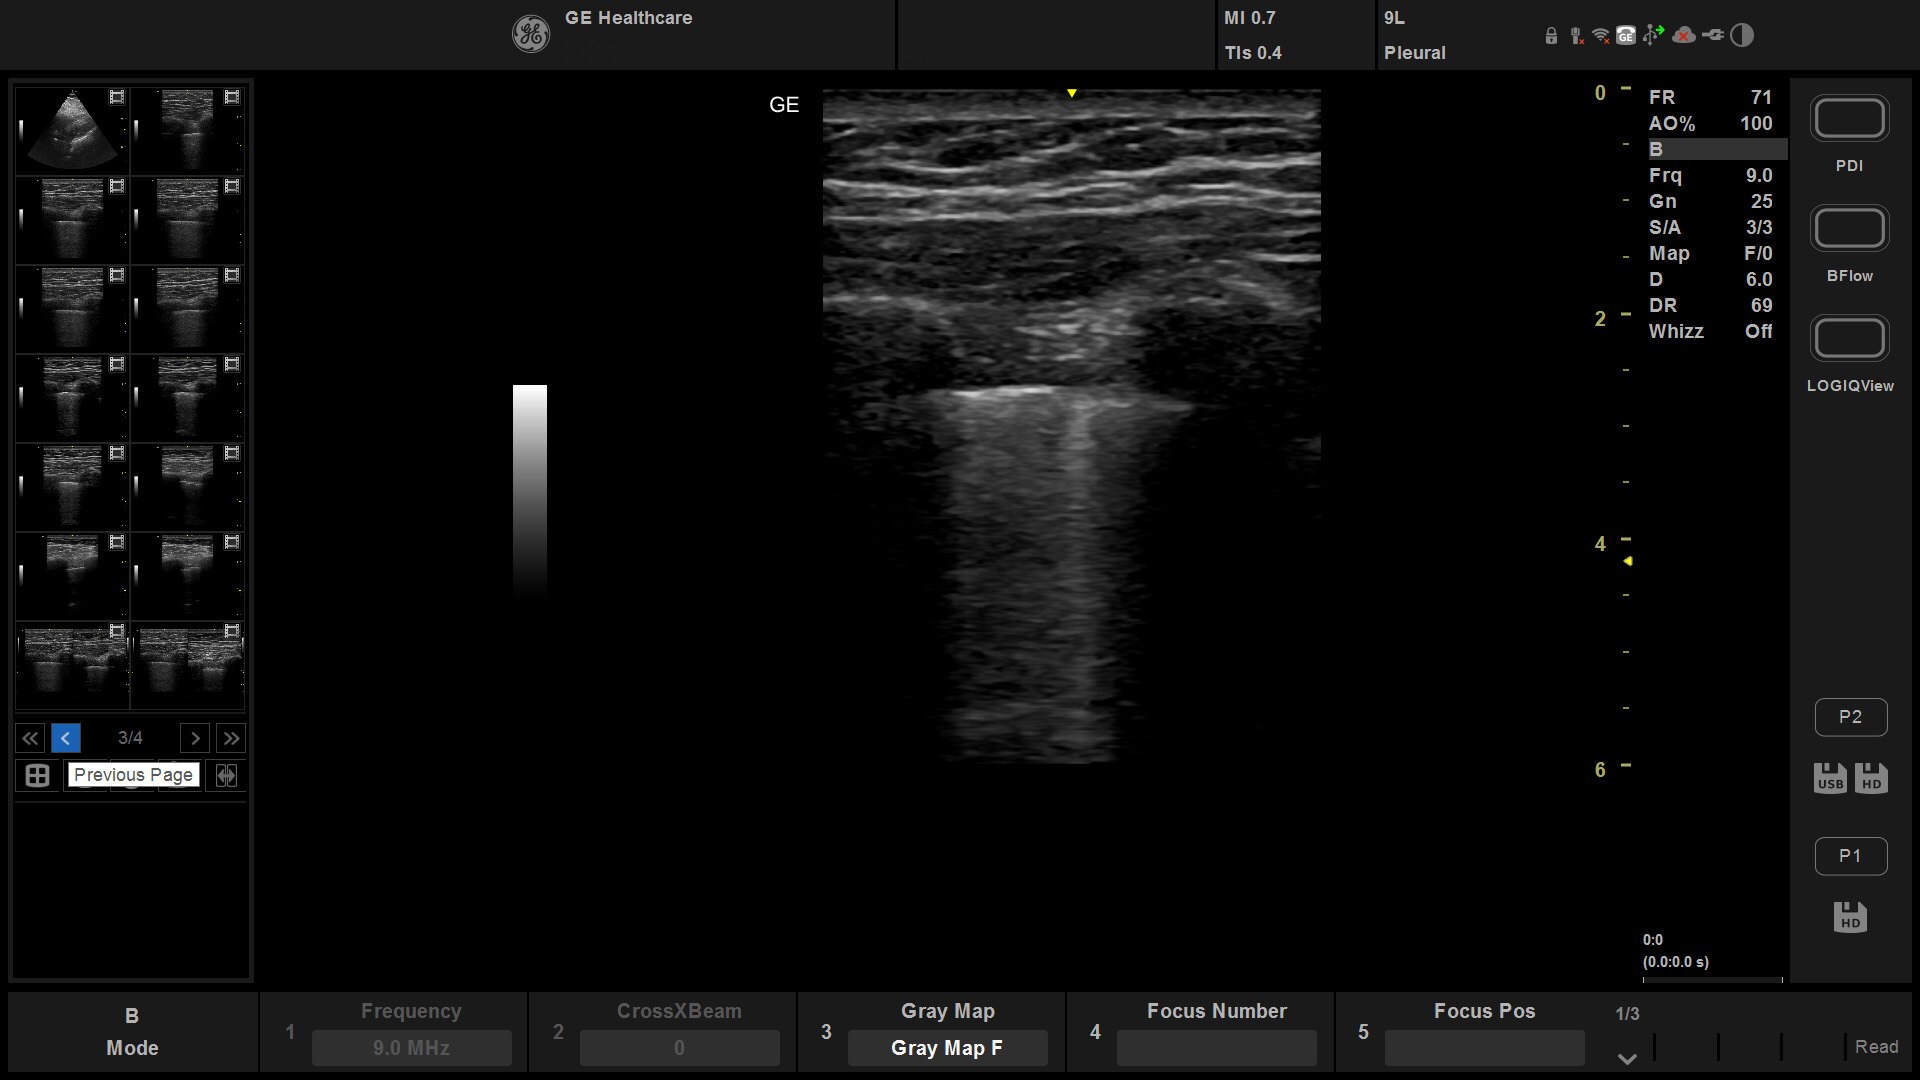

Suited for abdominal, small parts, cardiac, OB/GYN, vascular, and MSK exams

Versana Active delivers the imaging capability of a console in a hand-carried, lightweight package that enables you to actively take your system to your patients, on premises, or remote facilities. The reliable system brings the agility of a laptop unit with the capability for attaching to a cart. Adaptable to cover a broad range of everyday exams, it is easy to carry to clinics, offices, and beyond.

Versana Active features a wide range of advanced clinical applications and automated tools that simplify exams, streamline workflow, and enable fast, high-volume scanning to help you diagnose a wide spectrum of patient conditions.